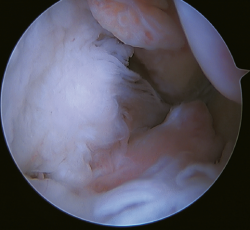

Otro punto de interés es la presencia de os subfibularis; en estos casos, existe la opción de la fijación, si bien no suele ser factible y la mejor opción terapéutica es su exéresis y reconstrucción, debido a la imposibilidad de realizar una reparación directa(60) (Figura 4).

Figura 5. Rotura del ligamento talofibular anterior y del ligamento calcaneofibular con mala calidad tisular del remanente ligamentoso.